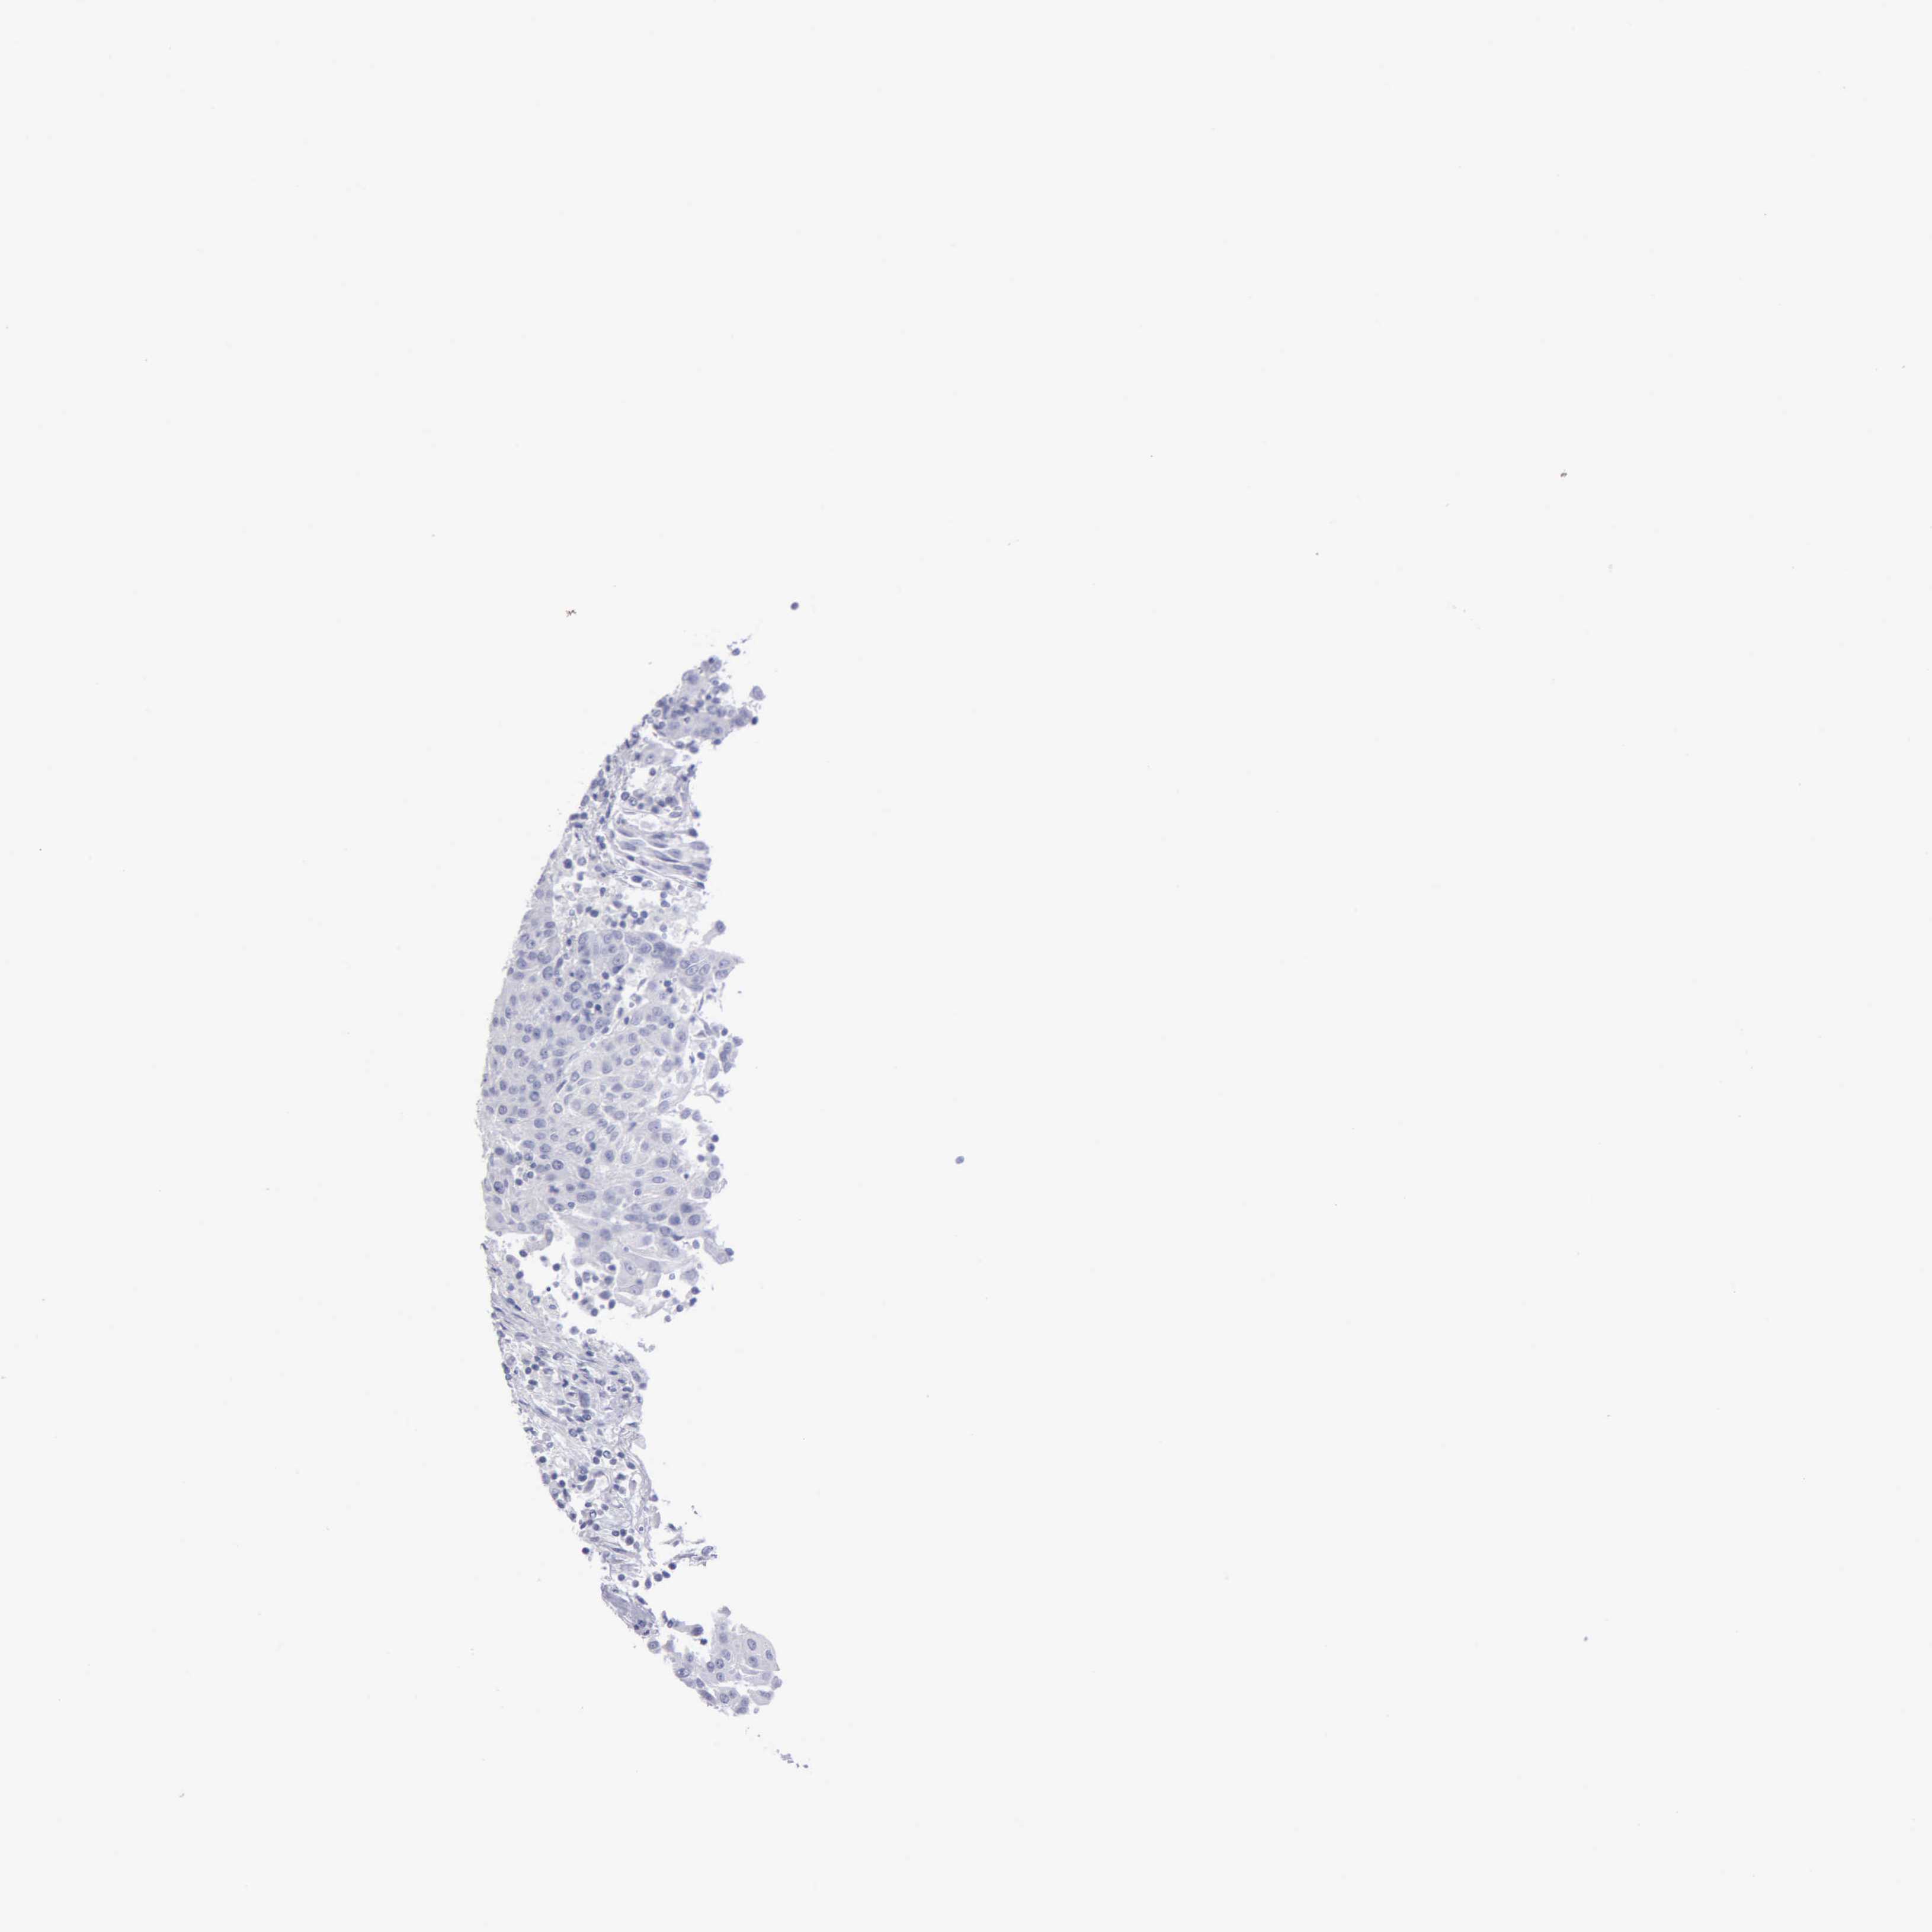

UROTHELIAL CANCER - Protein expressioni

A mouse-over function shows sample information and annotation data. Click on an image to view it in a full screen mode. Samples can be filtered based on level of antibody staining by selecting one or several of the following categories: high, medium, low and not detected. The assay and annotation is described here.

Note that samples used for immunohistochemistry by the Human Protein Atlas do not correspond to samples in the TCGA dataset.

Antibody stainingi

Antibody staining in the annotated cell types in the current human tissue is reported as not detected, low, medium, or high, based on conventional immunohistochemistry profiling in selected tissues. This score is based on the combination of the staining intensity and fraction of stained cells.

Each image is clickable and will lead to virtual microscopy that enables deeper exploration of all samples and also displays staining intensity scores, fraction scores and subcellular localization as well as patient and tissue information for each sample.

Antibody HPA000848

Antibody HPA000868

Antibody CAB025843

Staining

High

Medium

Low

Not detected

Intensity

Strong

Moderate

Weak

Negative

Quantity

>75%

75%-25%

<25%

None

Location

Nuclear

Cytoplasmic/membranous

Cytoplasmic/membranous,nuclear

Urothelial carcinoma, High grade

Urothelial carcinoma, Low grade